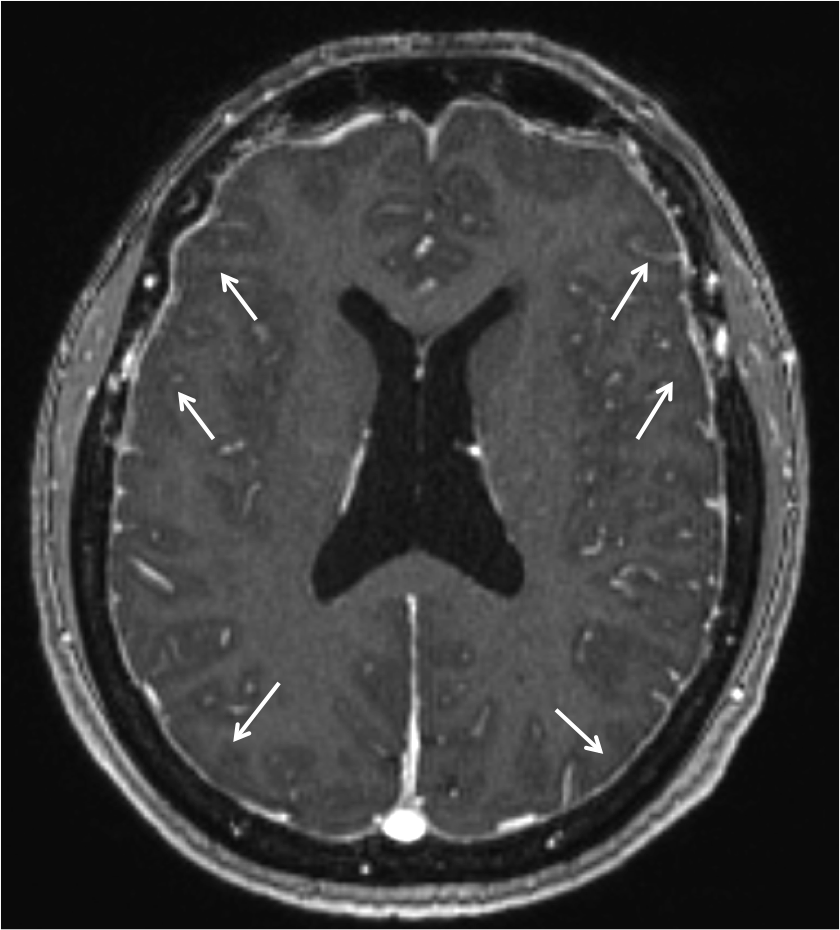

En la Imagen 6 y 7, se pude observar la captación dural de contraste que se debe a la mayor concentración de contraste (gadolinio) en la vasculatura y fluido intersticial de la duramadre. Esta hipercaptación afecta a la duramadre (paquimeninge) y no a las leptomeninges (aracnoides y piamadre) por lo que no afecta a la profundidad de los surcos corticales ni alrededor del tronco cerebral, es continuo no nodular y afecta a los compartimentos supra e infratentorial. En la Imagen 1 se observa también el engrosamiento dural sin contraste en fosa posterior y primeros segmentos cervicales.